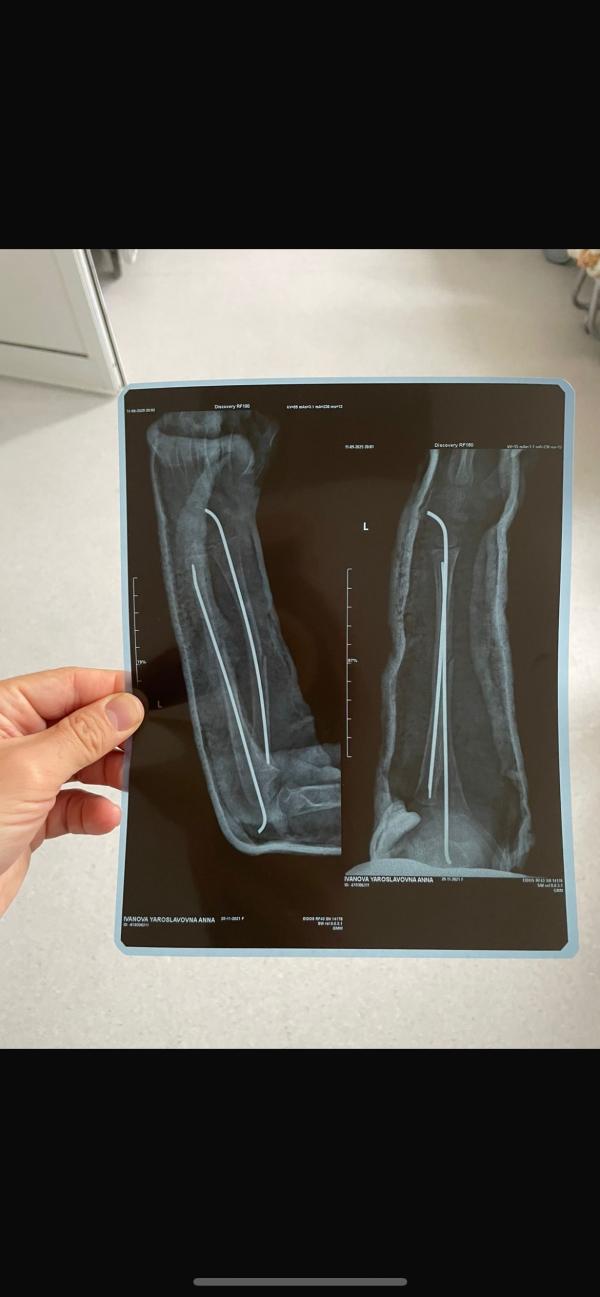

Мамы здравствуйте! Сегодня выписали дочку из больницы. Перелом обеих костей предплечья. Ставили спицы. С дочкой лежал муж и он не уточнил у врачей есть ли разрез на руке, швы? Может у кого была подобная ситуация, подскажите пожалуйста какого размера там шов?

У моей дочки были спицы, там нет швов совсем. Их вставляют через малюсенькую дырочку. Будут шрамики, когда снимут спицы, они почти не заметные. Она же в гипсе у вас?

У нас был перелом ключицы. Ставили спицы , швы по пол см.нескольк штук, ну как бы отверстия для спиц... И у нас они были прям сбоку торчали . Прошел год швы почти не заметны.